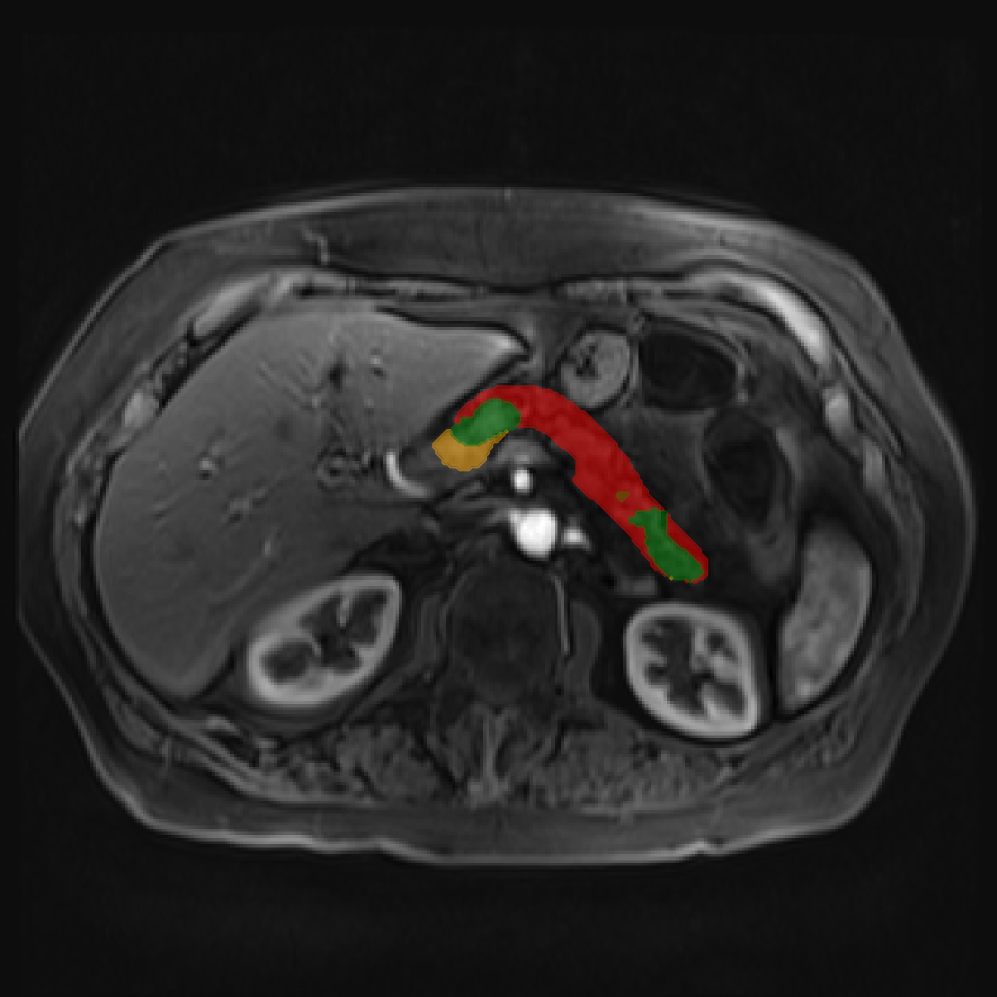

Accurate pancreas segmentation is a critical prerequisite for precise cyst analysis and classification. Recently, we developed PanSegNet [zhang2025large], a novel segmentation architecture incorporating linear self-attention layers [zhang2022dynamic] within the nnUNet framework [isensee2021nnu] to enhance global information modeling capabilities while maintaining computational efficiency (Fig. 1). PanSegNet demonstrated exceptional segmentation performance across both T1W and T2W modalities, achieving mean dice scores of 86.817.30% and 89.626.38%, respectively (Table 1, Fig. 2b-c). This performance significantly exceeded that of Swin-UNETR [hatamizadeh2021swin], one of the most used state-of-the-art transformer-based medical segmentation models, which achieved dice scores of 79.091.40% and 76.290.66% for T1W and T2W, respectively (). In this study, we integrated PanSegNet into our Cyst-X engine along with a classifier for risk prediction. In Section 2.2, we show that the choice of segmentation model affects the classification results. The performance advantage of PanSegNet was consistent across all seven medical centers, demonstrating robust generalization despite variations in imaging protocols and equipment (Table 1). This cross-institutional reliability is particularly important for clinical applications, where model performance must remain consistent regardless of imaging site or acquisition parameters.

2.2.1 Importance of accurate pancreas segmentation in classification

To assess the importance of accurate pancreas segmentation in classification, we evaluated how different ROI sources affect DenseNet-121’s performance. Specifically, we compared classification results using ROIs generated by PanSegNet and Swin-UNETR, both under centralized learning, against a baseline using radiologist-defined ROIs. As shown in Table 2, using PanSegNet’s masks resulted in only a modest performance decline, reflecting its strong segmentation quality. In contrast, Swin-UNETR led to a more substantial drop, demonstrating that inferior segmentation can directly compromise classification. For 3-class classification, the mean AUC dropped from 75.59% (radiologist ROI) to 72.26% with PanSegNet, and further to 66.95% with Swin-UNETR on T1-weighted images. On T2-weighted scans, the AUC declined from 81.09% to 74.18% (PanSegNet) and to 69.63% (Swin-UNETR). A similar trend was observed in 2-class classification: on T1W, AUC dropped from 78.13% to 74.84% (PanSegNet) and 70.20% (Swin-UNETR); on T2W, from 82.37% to 77.01% and 68.92%, respectively. These results emphasize that accurate segmentation—particularly via PanSegNet—is not only essential for volume estimation but also critical to preserving downstream classification performance in the Cyst-X pipeline.